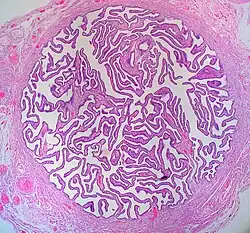

Стенка маточной трубы состоит из трех оболочек: слизистой, мышечной и серозной. Слизистая оболочка имеет многочисленные продольные складки (plicae tubariae). В эпителии слизистой оболочки имеются секреторные и реснитчатые клетки. Секреторные клетки вырабатывают необходимые для питания яйцеклетки вещества. Мышечная оболочка включает в себя циркулярные и продольные пучки гладких мышечных клеток. Перистальтические сокращения мышечной оболочки и мерцание ресничек эпителия обеспечивает продвижение яйцеклетки по яйцеводу в направлении к рогу матки. Внешняя серозная оболочка маточной трубы продолжающется в брыжейку маточной трубы (mesosalpinx) формирует широкую маточную связку (lig. latum uteri).